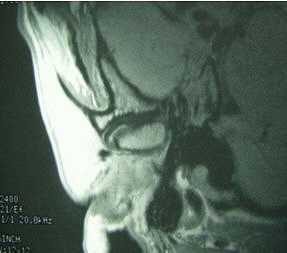

![]() |

Fifty-year-old woman with clicking and pain in both TMJs, 8-mm mandibular advancement, and MIO that decreased from 42 mm to 40 mm postoperative. Above, bilateral, right anterior disk displacement on MRI preoperative, which did not change on postoperative MRI, below. Images courtesy of Dr. Jessica Lee.